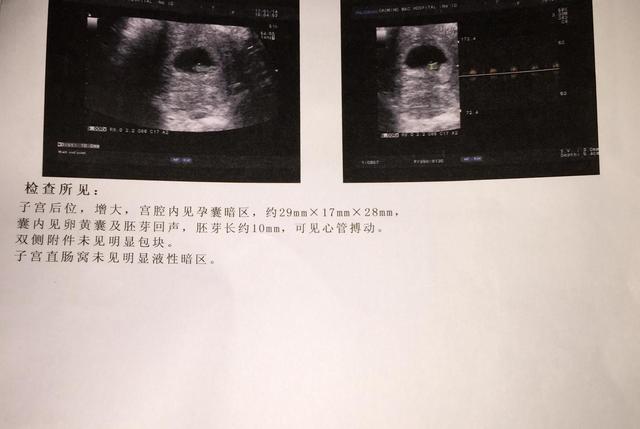

孕前月经规律,月经周期28-30天的女性,在孕35天左右,通过B超就可以看到胎囊的存在,到了孕6周左右,胎囊大约有2厘米大;孕10周左右,胎囊大约有5厘米,到了孕11周左右,胎囊则会逐渐消失。

正常情况下,胎囊会在子宫的宫底、前壁、后壁、上部或者是中间,大多数时候它们会是比较规律、且边缘清晰的圆形或者椭圆形,如果出现形状不规则或者边缘模糊,且在子宫下部,则有可能会发生流产。